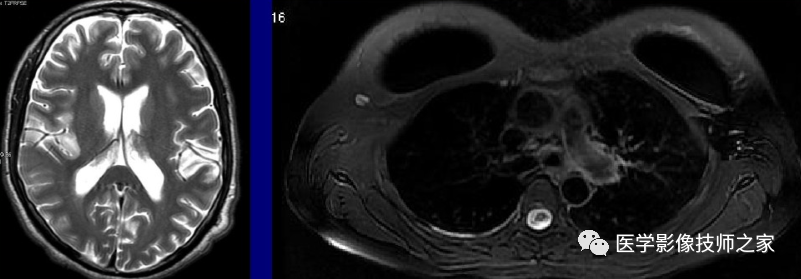

接收带宽是指 MR 系统采集 MR 信号时所接收的信号频率范围。减少接收带宽可以提高图像的信噪比,但可导致图像对比度下降。同时,减少扫描层数,扫描时间延长,并增加化学位移伪影。MR 激发脉冲使用的是射频波,其频率范围称为射频带宽或发射带宽。射频脉冲的持续时间越短,即脉冲的形状越窄,傅里叶变换后其频带带宽越宽。层面厚度与带宽成正比,即层厚越厚,带宽越宽。人体组织信号为不同频率信号的叠加, 包括被激励的组织和噪声。射频带宽越宽, 信号采集范围就越大, 噪声也越大。

1、SNR与RBW的平方根成反比,所以降低RBW可以在一定程度上提高SNR,但必须注意:过低的RBW会使MinTE或ESP增加,故在T1加权像过低RBW可导致T1对比度变差,而在T2加权像则可能导致模糊伪影加重

2、1.5TRBW一般设定大于31kHz